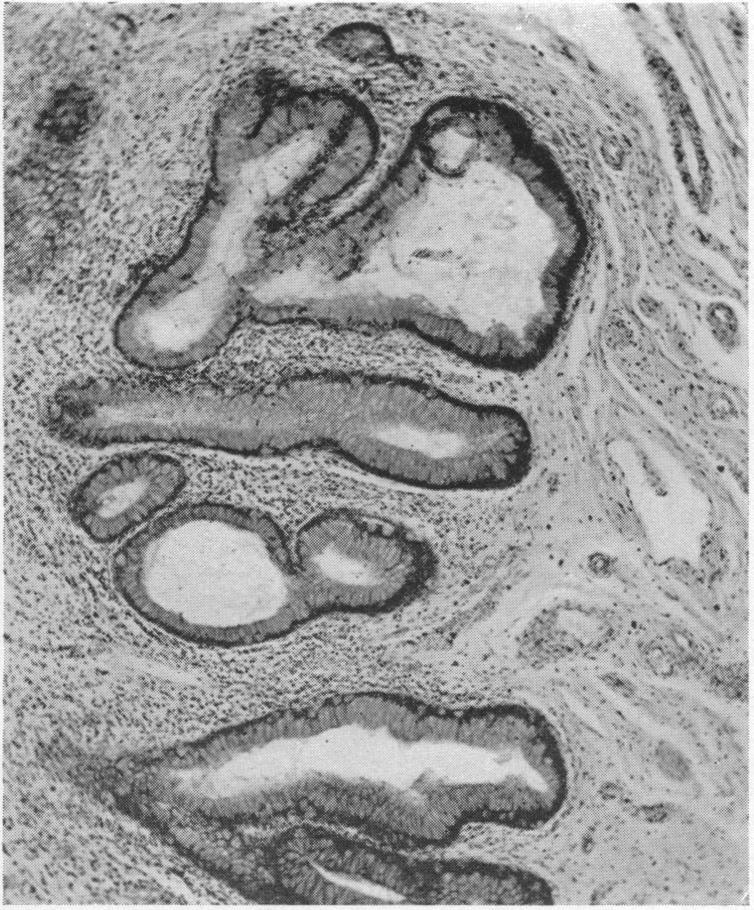

THE POTENTIAL MALIGNANCY IN EXSTROPHY OF THE BLADDER.

Ann Surg. 1922 Mar;75(3):365-71. doi: 10.1097/00000658-192203000-00008.